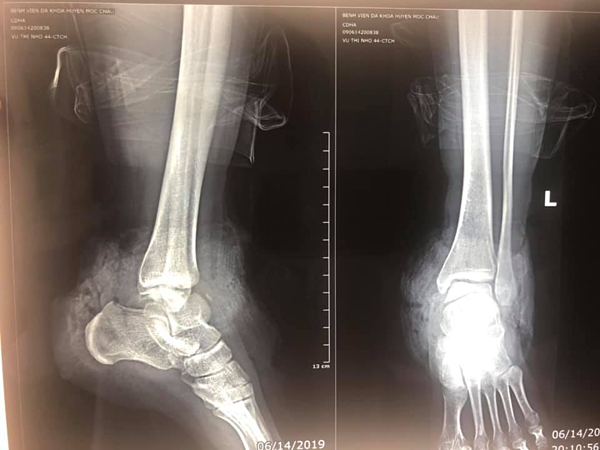

Ảnh chụp cổ chân bị đứt lìa được các bác sĩ nối thành công.

Theo nguồn tin đăng tải trên báo Vnexpress, tối 14/6, Bệnh viện Đa khoa huyện Mộc Châu, tỉnh Sơn La, tiếp nhận bệnh nhân 44 tuổi, là giáo viên trường mầm non, nhập viện trong tình trạng sốc do mất máu nhiều. Bệnh nhân bị đứt gần hoàn toàn cổ chân trái do tai nạn, nếu chuyển lên tuyến trên, thời gian di chuyển quá lâu sẽ dễ dẫn đến nguy cơ phải cắt cụt chân.

Kíp bác sĩ nhanh chóng tiến hành hội chẩn, quyết định mổ ngay tại bệnh viện huyện. May mắn sau hơn 3 giờ phẫu thuật, kíp mổ đã nối thành công 7 mạch máu gồm 2 động mạch và 4 tĩnh mạch, 2 dây thần kinh và toàn bộ gân.